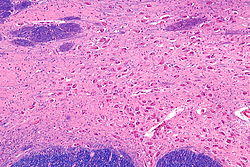

Nucleus basalis of Meynert - intermed mag.jpg

Intermediate magnification micrograph of the nucleus basalis. LFB-HE stain.